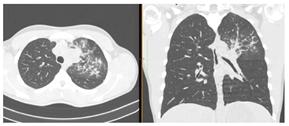

2. Наличие клинических проявлений, указанных в п. 1, в сочетании с характерными изменениями в легких по данным компьютерной томографии (КТ) (см. Приложение 1 настоящих рекомендаций) вне зависимости от результатов однократного лабораторного исследования на наличие РНК SARS-CoV-2 и эпидемиологического анамнеза.

- Изменения при КТ (рентгенографии), типичные для вирусного поражения (объем поражения минимальный или средний; КТ 1-2)

- Изменения в легких при КТ (рентгенографии), типичные для вирусного поражения (объем поражения значительный или субтотальный; КТ 3-4)

- Изменения в легких при КТ (рентгенографии), типичные для вирусного поражения критической степени (объем поражения значительный или субтотальный; КТ 4) или картина ОРДС.

КТ имеет высокую чувствительность в выявлении изменений в легких, характерных для COVID-19. Применение КТ целесообразно для первичной оценки состояния ОГК у пациентов с тяжелыми прогрессирующими формами заболевания, а также для дифференциальной диагностики выявленных изменений и оценки динамики процесса. КТ позволяет выявить характерные изменения в легких у пациентов с COVID-19 еще до появления положительных лабораторных тестов на инфекцию с помощью МАНК. В то же время, КТ выявляет изменения легких у значительного числа пациентов с бессимптомной и легкой формами заболевания, которым не требуется госпитализация. Результаты КТ в этих случаях не влияют на тактику лечения и прогноз заболевания при наличии лабораторного подтверждения COVID-19. Поэтому массовое применение КТ для скрининга асимптомных и легких форм болезни не рекомендуется.